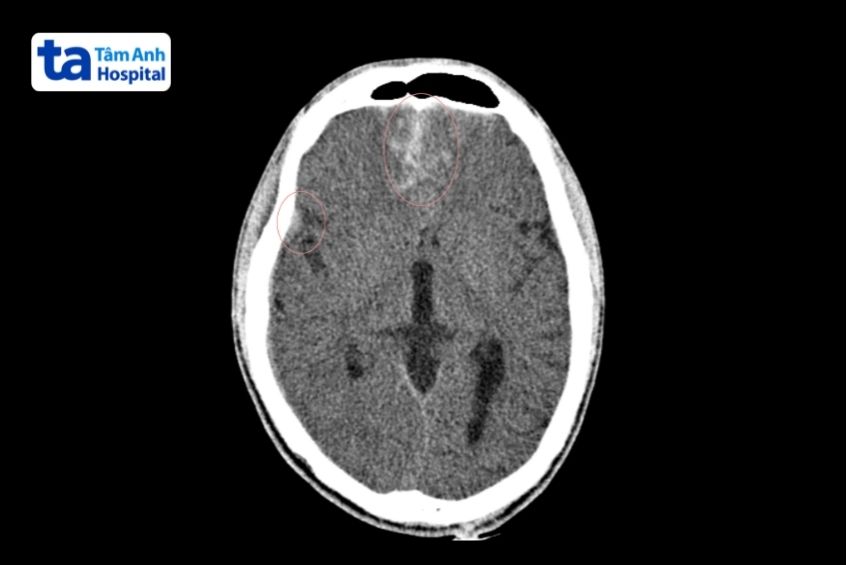

3. Hình ảnh dập não trong chấn thương

Dập não xuất hiện trên CT là một vùng giảm tỷ trọng do phù nề, xen kẽ các điểm tăng tỷ trọng của ổ xuất huyết. Vùng tổn thương thường gây hiệu ứng choán chỗ vì phù não lan rộng. Nguyên nhân chủ yếu do chảy máu trong nhu mô não tại khu vực gần xương sọ, nơi chịu tác động va đập. Tuy nhiên, đôi khi tổn thương lại xuất hiện ở phía đối diện với chỗ va đập, do lực phản hồi trong quá trình chấn thương.

Ảnh chụp CT phát hiện dập não do chấn thương